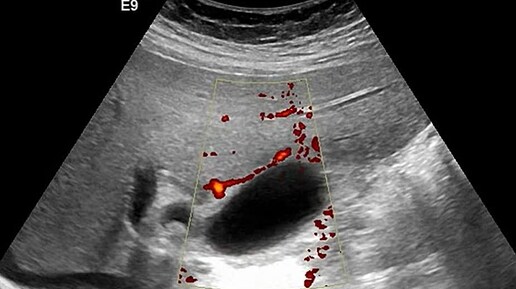

Ультразвуковые находки от врача УЗД Зорина Я.П.